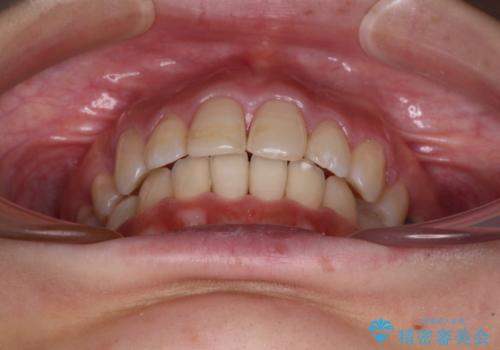

突出した口元が気になる ハーフリンガル装置による抜歯矯正

ハーフリンガルは、通常では表側のワイヤー矯正よりも治療期間がかかります。特に今回のように下顎左側をイレギュラーの第二小臼歯抜歯としたため、さらに時間がかかることが予想されました。

実際に治療をおこなってみると、2年を切る短期間で治療を終えることができました。